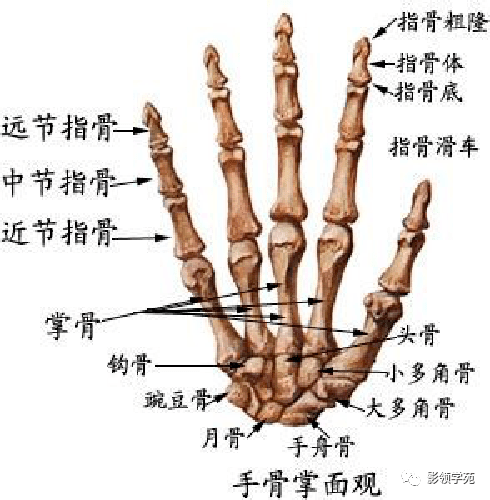

骨骼系统

骨骼系统